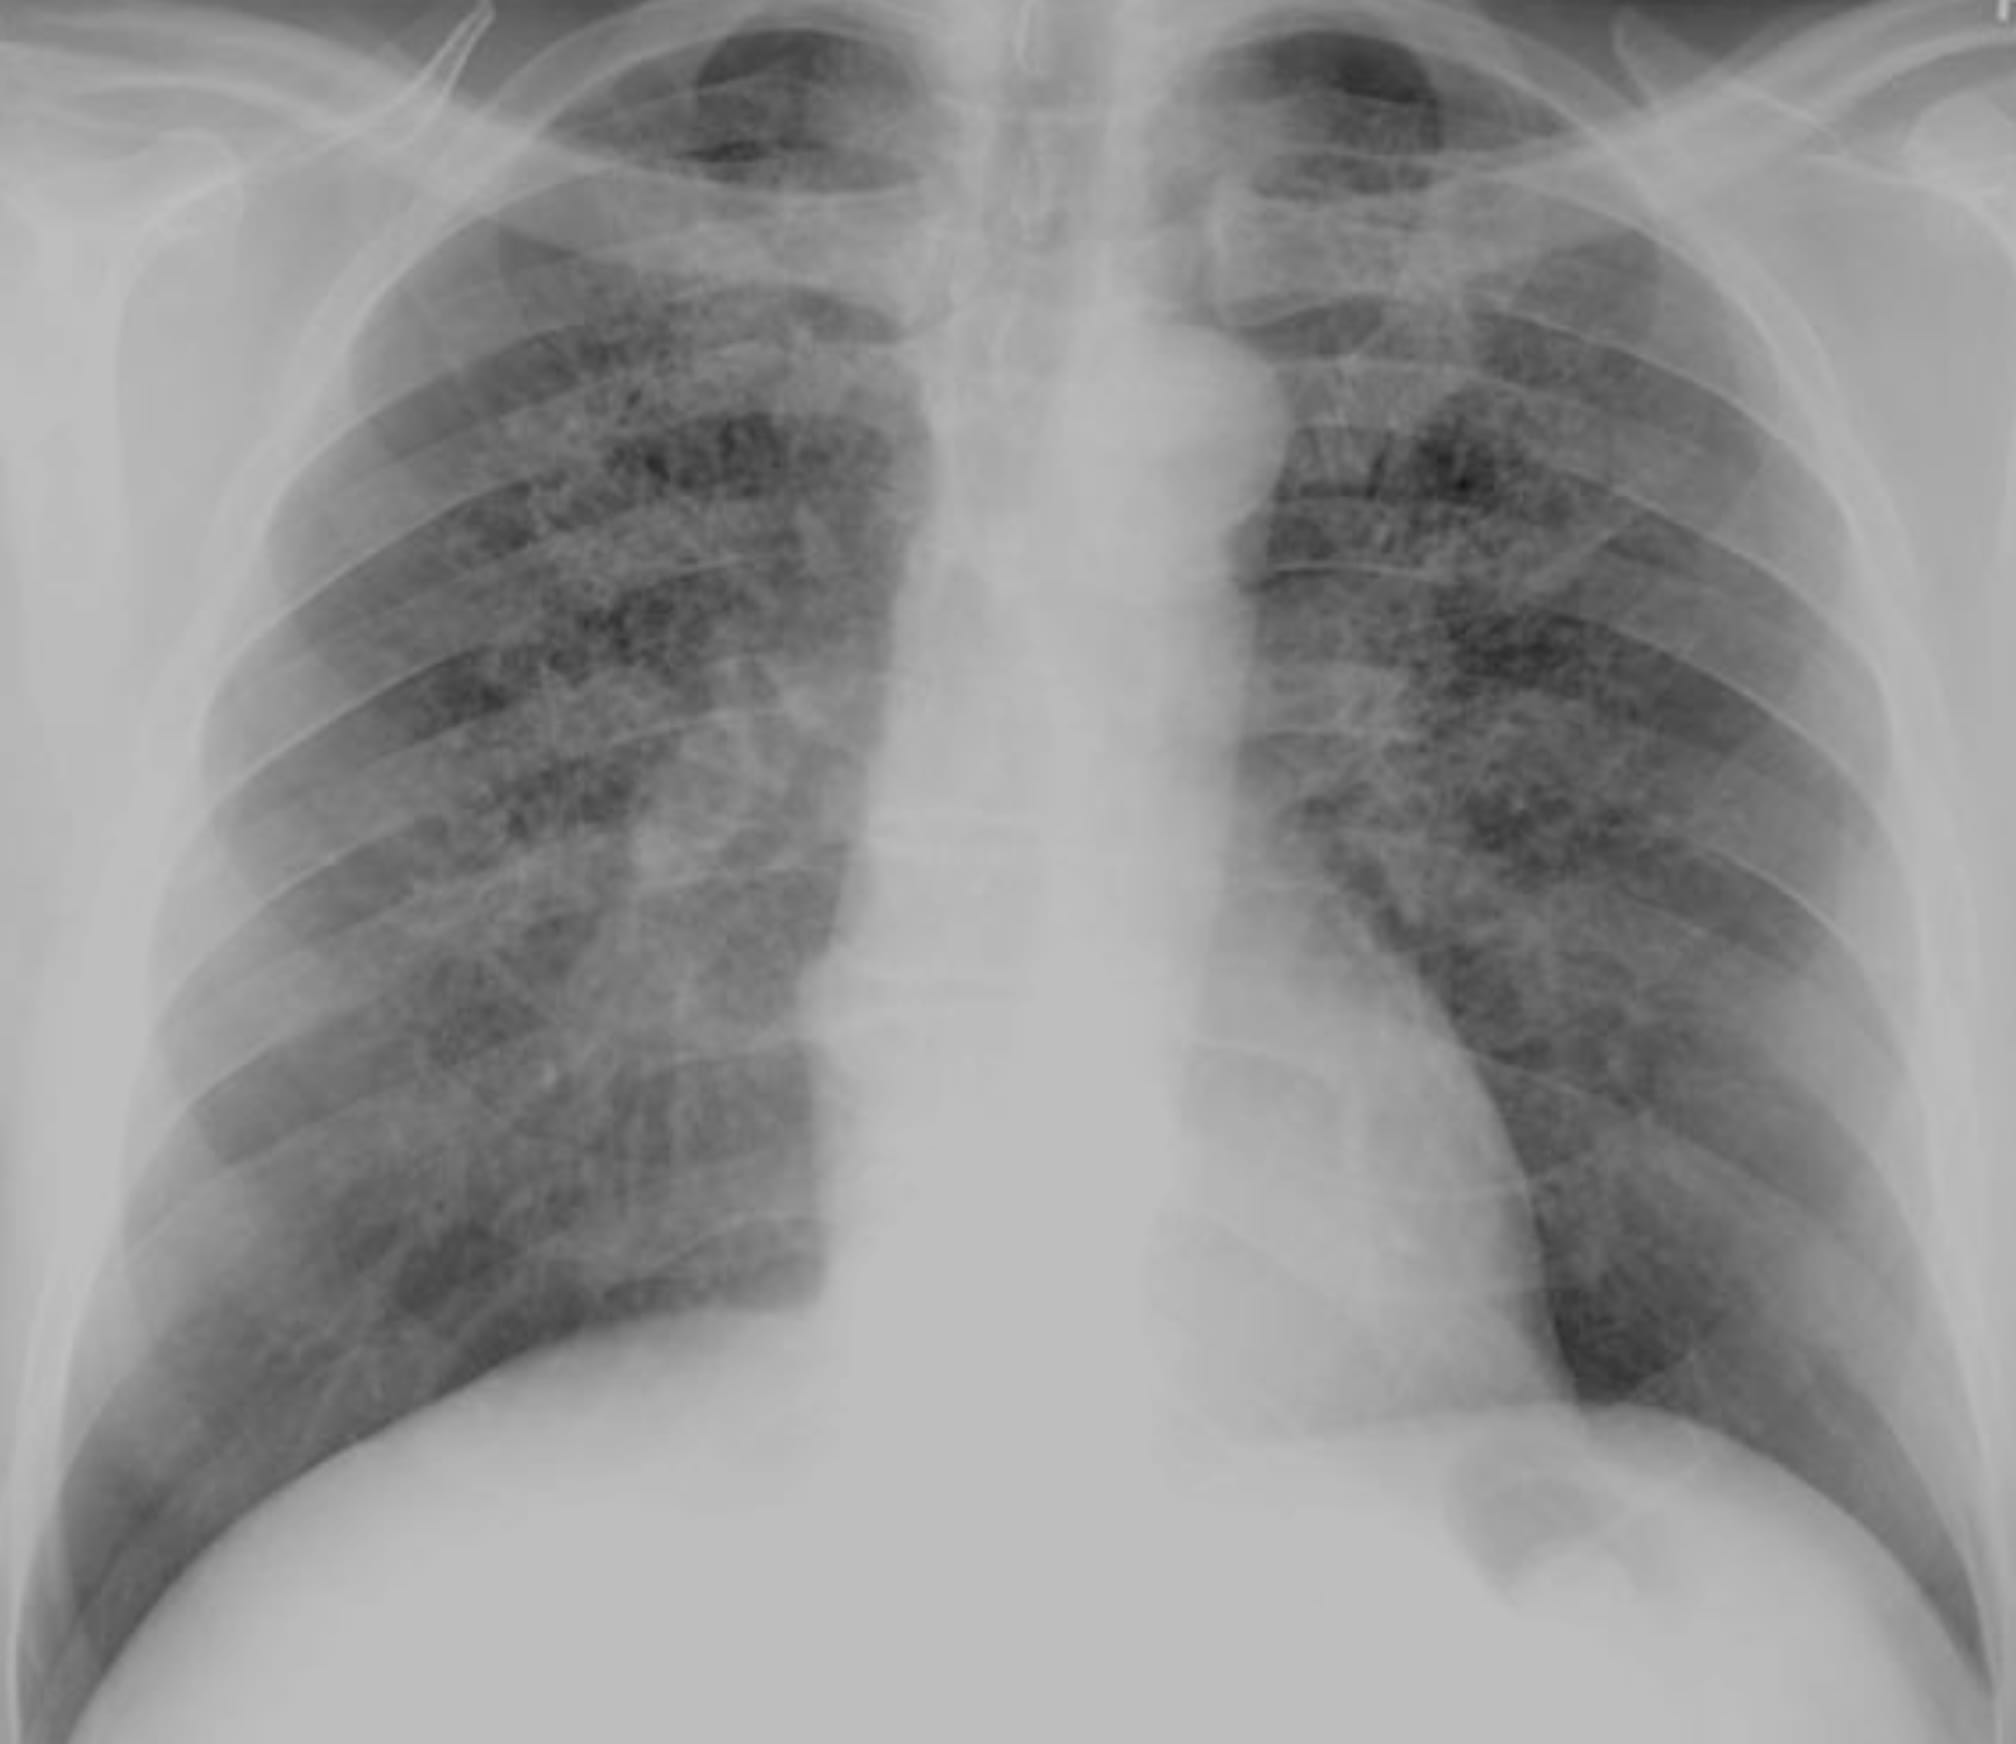

Key Points

Note the predominant involvement of the upper lungs.

The very definition of an Aunt Minnie